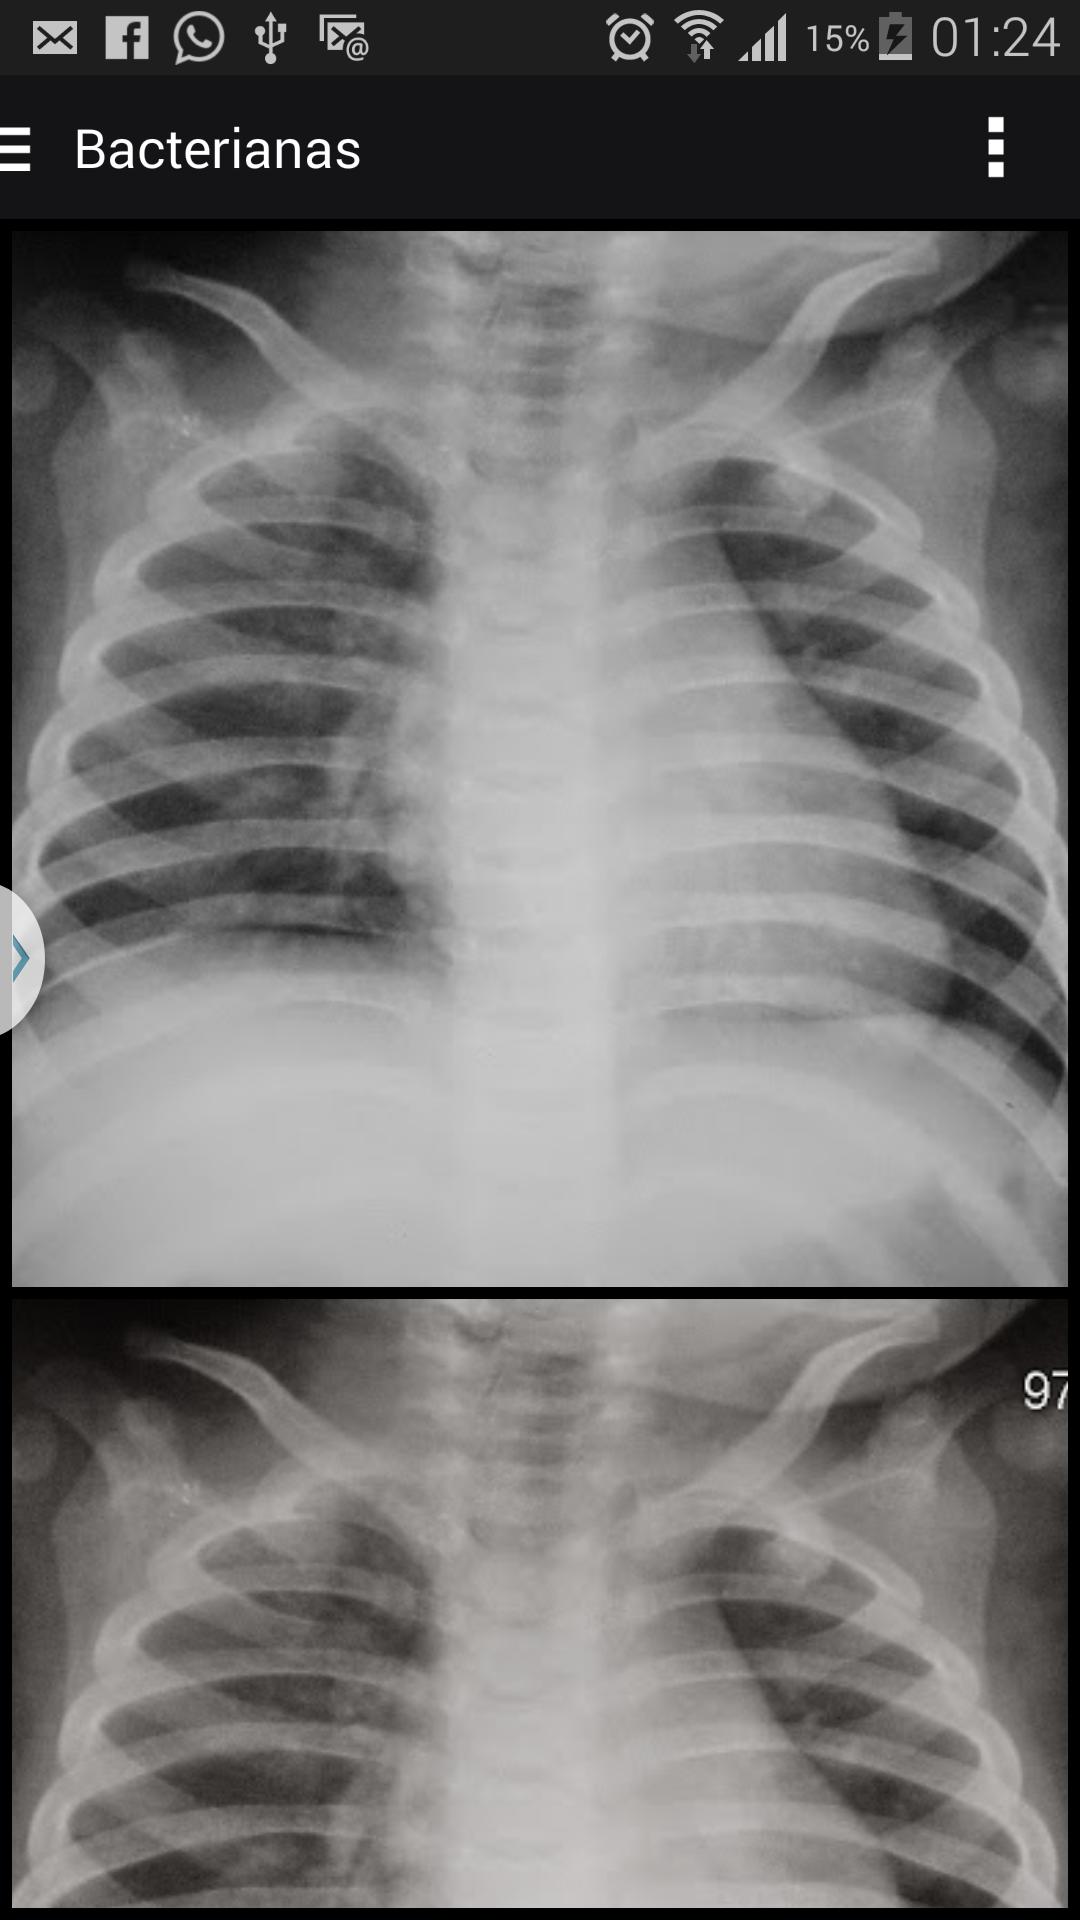

صور الأشعة السينية لدعم تشخيص الالتهاب الرئوي عند الأطفال

أثبتت أهمية الالتهاب الرئوي كسبب لوفيات الأطفال في البرازيل على النحو الواجب في الوثائق الصحية الأخيرة. الالتهاب الرئوي هو أهم سبب لوفيات الطفولة ، حيث يحتل السبب الثاني لوفيات الأطفال في البلدان النامية ، بما في ذلك البرازيل.

تعتبر منظمة الصحة العالمية من قبل منظمة الصحة العالمية (WHO) أفضل طريقة متاحة حاليًا لتشخيص الالتهاب الرئوي في الممارسة السريرية اليومية. تعتبر الدراسات التي أجريت على تباين interobserving شائعًا في جميع مجالات الطب ، ومع ذلك ، تسود في دراسات الصور ، بالنظر إلى أنه في هذا المجال ، يمثل أداء المراقب الجزء الهش ، يتناقض مع التقدم التكنولوجي ، الذي تم الحصول عليه في العقد الماضي.

يمكن أن تسمى التفسيرات التي تختلف عن "إجماع" من قبل لجنة مراقب من ذوي الخبرة "خطأ". يحدث التباين بين المراقبين عندما يكون هناك خطأ من قبل المراقب ، ولكنه يتضمن أيضًا الحالات التي يوجد فيها اختلاف في الرأي العام حول ما يمثله التفسير الصحيح. تمت دراسة الأخطاء والتغيرات بشكل خاص في تفسير الصور الشعاعية.

الذهب "العامل الأساسي في تقييم الاختبارات التشخيصية. في حالة التشخيص الشعاعي للصدر ، وخاصة في مرحلة الطفولة ، يتم تقييم الدقة في تفسير الصورة بشكل ذاتي من خلال اتفاق inter و intraobserving ، حيث نادرا ما يكون هناك نمط يمكن استخدامه كمرجع (معيار) في تشخيص التهاب الرئة.